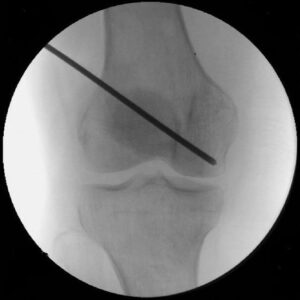

- This procedure involves drilling one or more holes into the affected bone to alleviate pressure, improve circulation, and encourage the growth of new blood vessels.

- Early Diagnosis Benefit: When performed in the early stages of osteonecrosis, core decompression can prevent bone collapse and the progression to arthritis.

Core decompression on a patient with early stage osteonecrosis.